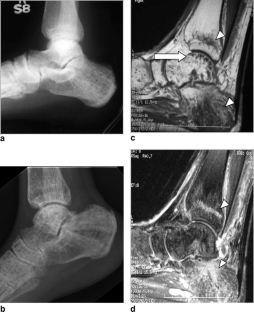

Fibrogenesis imperfecta ossium: MR imaging of the axial and appendicular skeleton and correlation with a unique radiographic appearance

We describe a distinctly unusual MR appearance of the cancellous bone never before described in a patient with biopsy-proven fibrogenesis imperfecta ossium.

Fig. 2